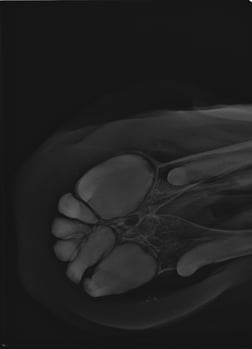

Wurzelverdickung Röntgen

Verdickung der Wurzel